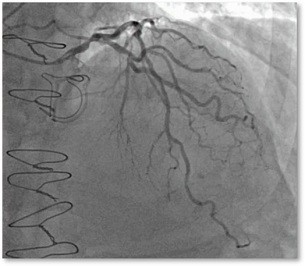

Multi Vessel Disease

Ensure cost-efficiency in your Multi-vessel Disease cases.

Multi-vessels coronary artery disease (CAD) is a disease stage in which at least two or three of the epicardial coronary arteries is involved with atherosclerosis of significant severity.

The goal in the treatment of multi-vessel disease is to reduce angina and heart failure symptoms.

The FAME study demonstrated that routine measurement of FFR (Fractional Flow Reserve) during DES-stenting in patients with multi-vessel disease is superior to current angiography guided treatment and improves outcome of PCI significantly.

From a short time, we also see some non Hyperemic index's been developed such as DFR™.  The goal of these indexs are to avoid injection of adenosine. It may reduce cost and duration procedure. It also may lead to assess patient who are contraindicated to FFR.